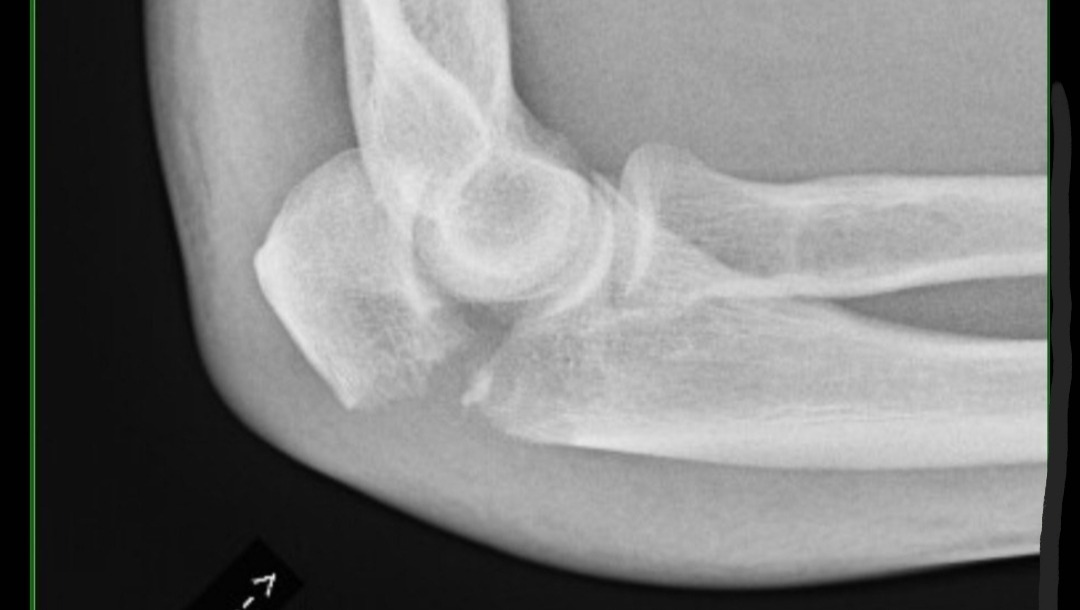

Joey now has a totaled motorcycle and a severely broken elbow. We are incredibly fortunate that he is here today and suffered as few injuries as he did. *there is an X-ray image at the very bottom of this post showing Joey's elbow*

Joey will need an open reduction and internal fixation procedure, where doctors will surgically reposition and stabilize the bone. This surgery has a painful healing process that will leave him unable to work for a minimum of 6 weeks.